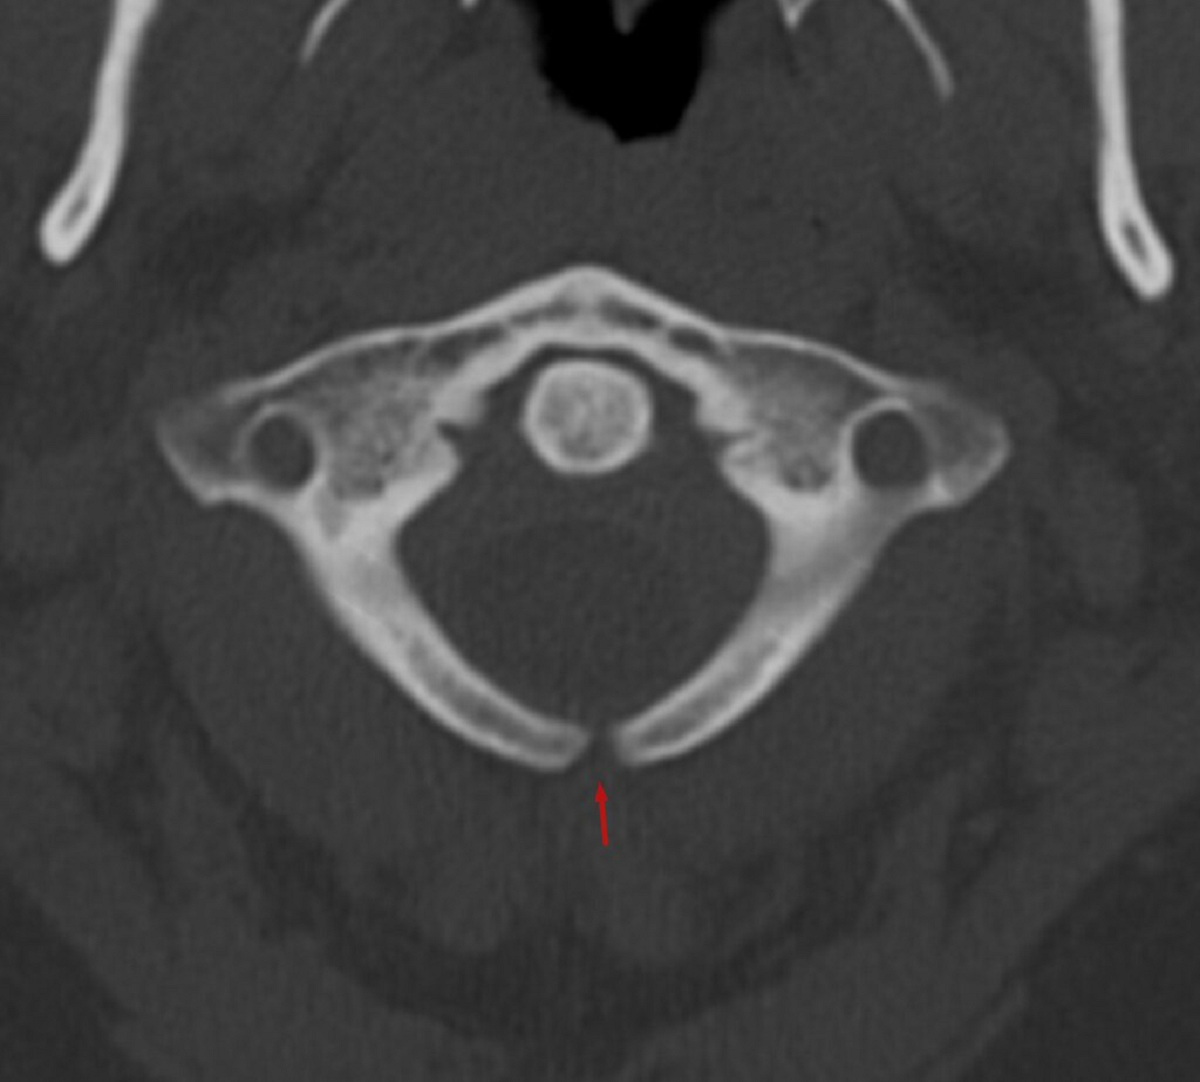

Riječ je o jednoj od najčešćih kongenitalnih anomalija središnjeg živčanog sustava, koja nastaje u ranom stadiju trudnoće kada se neuralna cijev iz koje se razvijaju ove strukture ne zatvori u potpunosti.